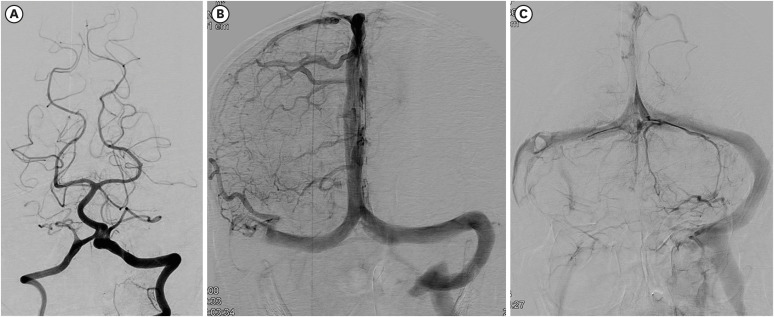

Spontaneous breathing recovered and the patient was weaned off the mechanical ventilator on the second day of intubation. He showed no improvement in consciousness. Brain magnetic resonance imaging (MRI) was performed to evaluate his poor consciousness on the eighth day of respiratory arrest. Ill-defined hyperintense lesions were noted on the right medulla, pons, and some parts of the right cerebellum on T2-weighted images. The lesions mainly showed high signal intensity on diffusion-weighted images with a high apparent diffusion coefficient (ADC) value on ADC map, indicating vasogenic edema. There was an intralesional hemorrhage of dark SI on T2* gradient echo images and small cytotoxic edema in an area of restricted diffusion in the right pons and medulla (FIGURE 3A-H). These findings were compatible with neuroimaging findings suggesting venous infarction induced by venous congestion. We started low-molecular-weight heparin (enoxaparin 6,000 IU every 12 hours, subcutaneously) and continued for approximately 72 hours. Unfortunately, the cerebral hemispheres showed diffuse changes compatible with hypoxic brain injury on MRI taken after 8 days from respiratory arrest (FIGURE 3I-K). The right sigmoid sinus and jugular vein were occluded on magnetic resonance (MR) venography underwent 9 days after respiratory arrest. On 23th days from respiratory arrest, no injury was observed in the vertebrobasilar artery on catheter cerebral angiography (FIGURE 4A). The right petrosal vein and sinus were not traced, and contrast-filling defects on the right sigmoid sinus and jugular vein were noted on cerebral angiography (FIGURE 4B & C). Conservative treatment was provided for pneumonia, and the patient was tracheostomized. Unfortunately, he did not regain consciousness and survived for only 2 years.

FIGURE 4. Cerebral catheter angiogram of the case (23th day of respiratory arrest). No arterial abnormalities were revealed on vertebral angiography (A). However, the right sigmoid sinus and jugular bulb were not visualized (B) in the venous phase on the right carotid angiogram, and the right jugular bulb was obliterated and some of the venous channels on the right posterior fossa were not visualized (C).